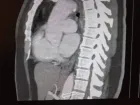

Case report: We report here the case of a 28 year-old male with no medical history who was admitted to the emergency room for severe abdominal pain. Computerized Tomography angiography (CT) scan revealed portal vein thrombosis. Laboratory findings showed pancytopenia with severe regenerative normocytic anemia resulting in PNH. Because of the lack of Eculizumab, treatment was first based on curative anticoagulation until bone marrow transplant, with no success.

Figure 1